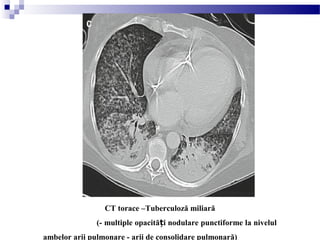

Tuberculoză miliară

(- multiple opacită i nodulare punctiforme la nivelul ambelorț

arii pulmonare - arie focală de consolidare la nivelul lobului mijlociu drept)

CT torace –Tuberculoză miliară

(- multiple opacită i nodulare punctiforme la nivelulț

ambelor arii pulmonare - arii de consolidare pulmonară)